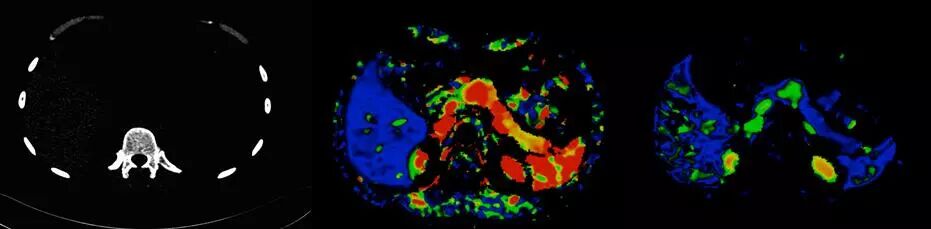

5D功能成像

6.低劑量全臟器灌注和動態(tài)血流成像:

超大范圍80厘米功能成像,只需要一次平掃的輻射劑量,既可完成一站式全器官灌注掃描(神經(jīng)、體部、心?。┖蛣討B(tài)血流評估,更安全而全面的獲取形態(tài)學(xué)和功能學(xué)信息。

△肝臟5D灌注,本底輻射劑量,取代傳統(tǒng)多期相掃描